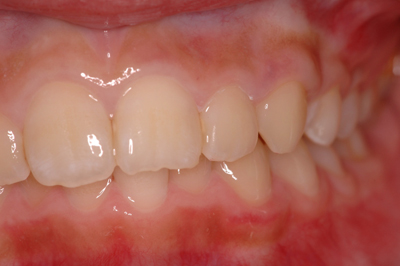

インプラント施術例

歯を削りたくない、入れ歯をどうしても入れたくないという時、インプラント治療を行っています。

施術前

施術後